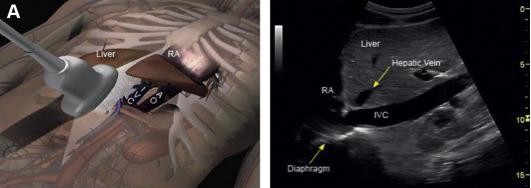

而超声ΔIVC预测液体反应性的准确性是可接受的。检测方式包括下腔静脉内径(IVC)形变指数、IVC扩张指数或IVC变异指数,阈值为11.1%~49.0%。ΔIVC预测液体反应的灵敏度为75%、特异性为83%。

注:图像来源为Kaptein MJ,et al..2021;28(3):218-226.

图5 IVC超声探头位置及超声图像